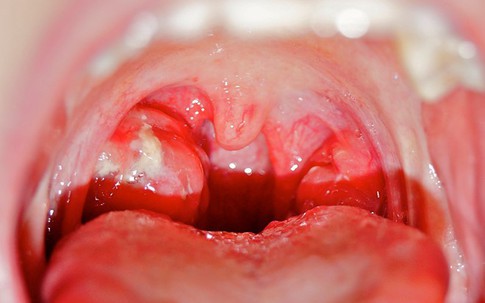

10 dấu hiệu ung thư máu mọi người cần cảnh giác

Sống khỏe

Vết bầm tím không do va đập, đau khớp, sốt kéo dài, chảy máu nướu, đổ mồ hôi ban đêm... cảnh báo bạn bị ung thư máu, theo PCC.